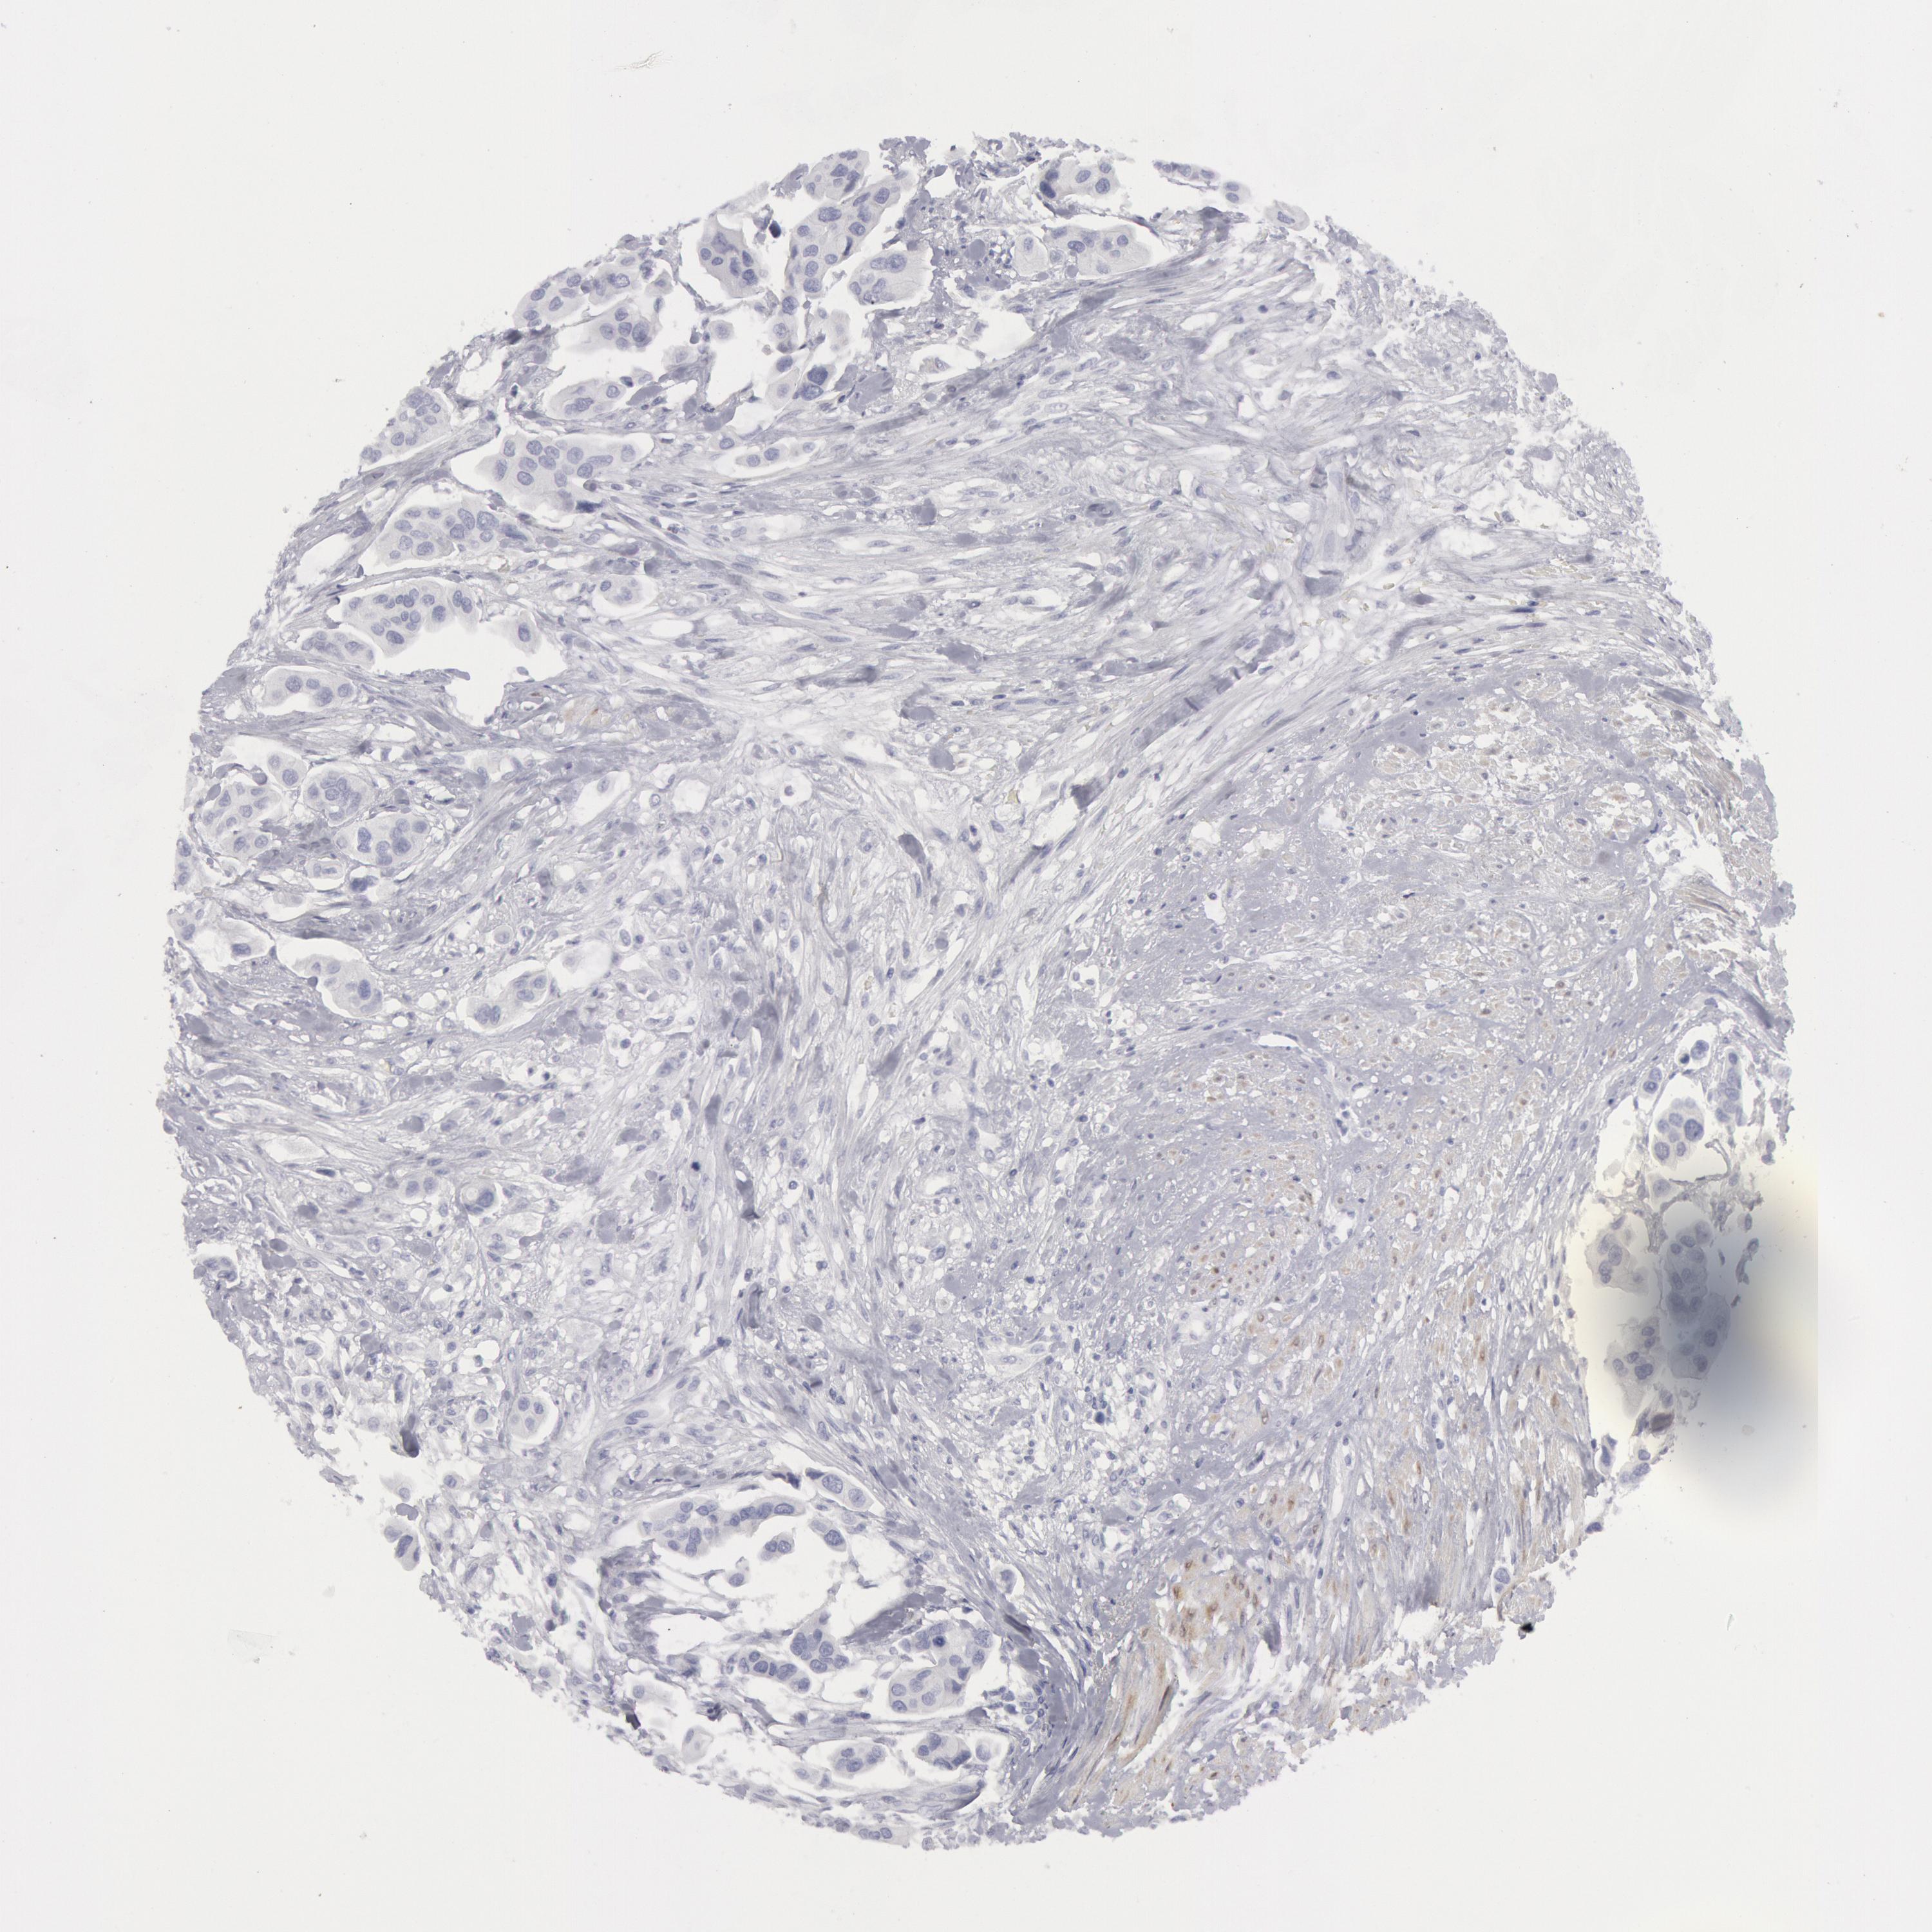

UROTHELIAL CANCER - Protein expressioni

A mouse-over function shows sample information and annotation data. Click on an image to view it in a full screen mode. Samples can be filtered based on level of antibody staining by selecting one or several of the following categories: high, medium, low and not detected. The assay and annotation is described here.

Note that samples used for immunohistochemistry by the Human Protein Atlas do not correspond to samples in the TCGA dataset.

Antibody stainingi

Antibody staining in the annotated cell types in the current human tissue is reported as not detected, low, medium, or high, based on conventional immunohistochemistry profiling in selected tissues. This score is based on the combination of the staining intensity and fraction of stained cells.

Each image is clickable and will lead to virtual microscopy that enables deeper exploration of all samples and also displays staining intensity scores, fraction scores and subcellular localization as well as patient and tissue information for each sample.

Antibody HPA001040

Antibody HPA001391

Antibody CAB020817

Staining

High

Medium

Low

Not detected

Intensity

Strong

Moderate

Weak

Negative

Quantity

>75%

75%-25%

<25%

None

Location

Nuclear

Cytoplasmic/membranous

Cytoplasmic/membranous,nuclear

Urothelial carcinoma, High grade

Urothelial carcinoma, Low grade

Adenocarcinoma, NOS